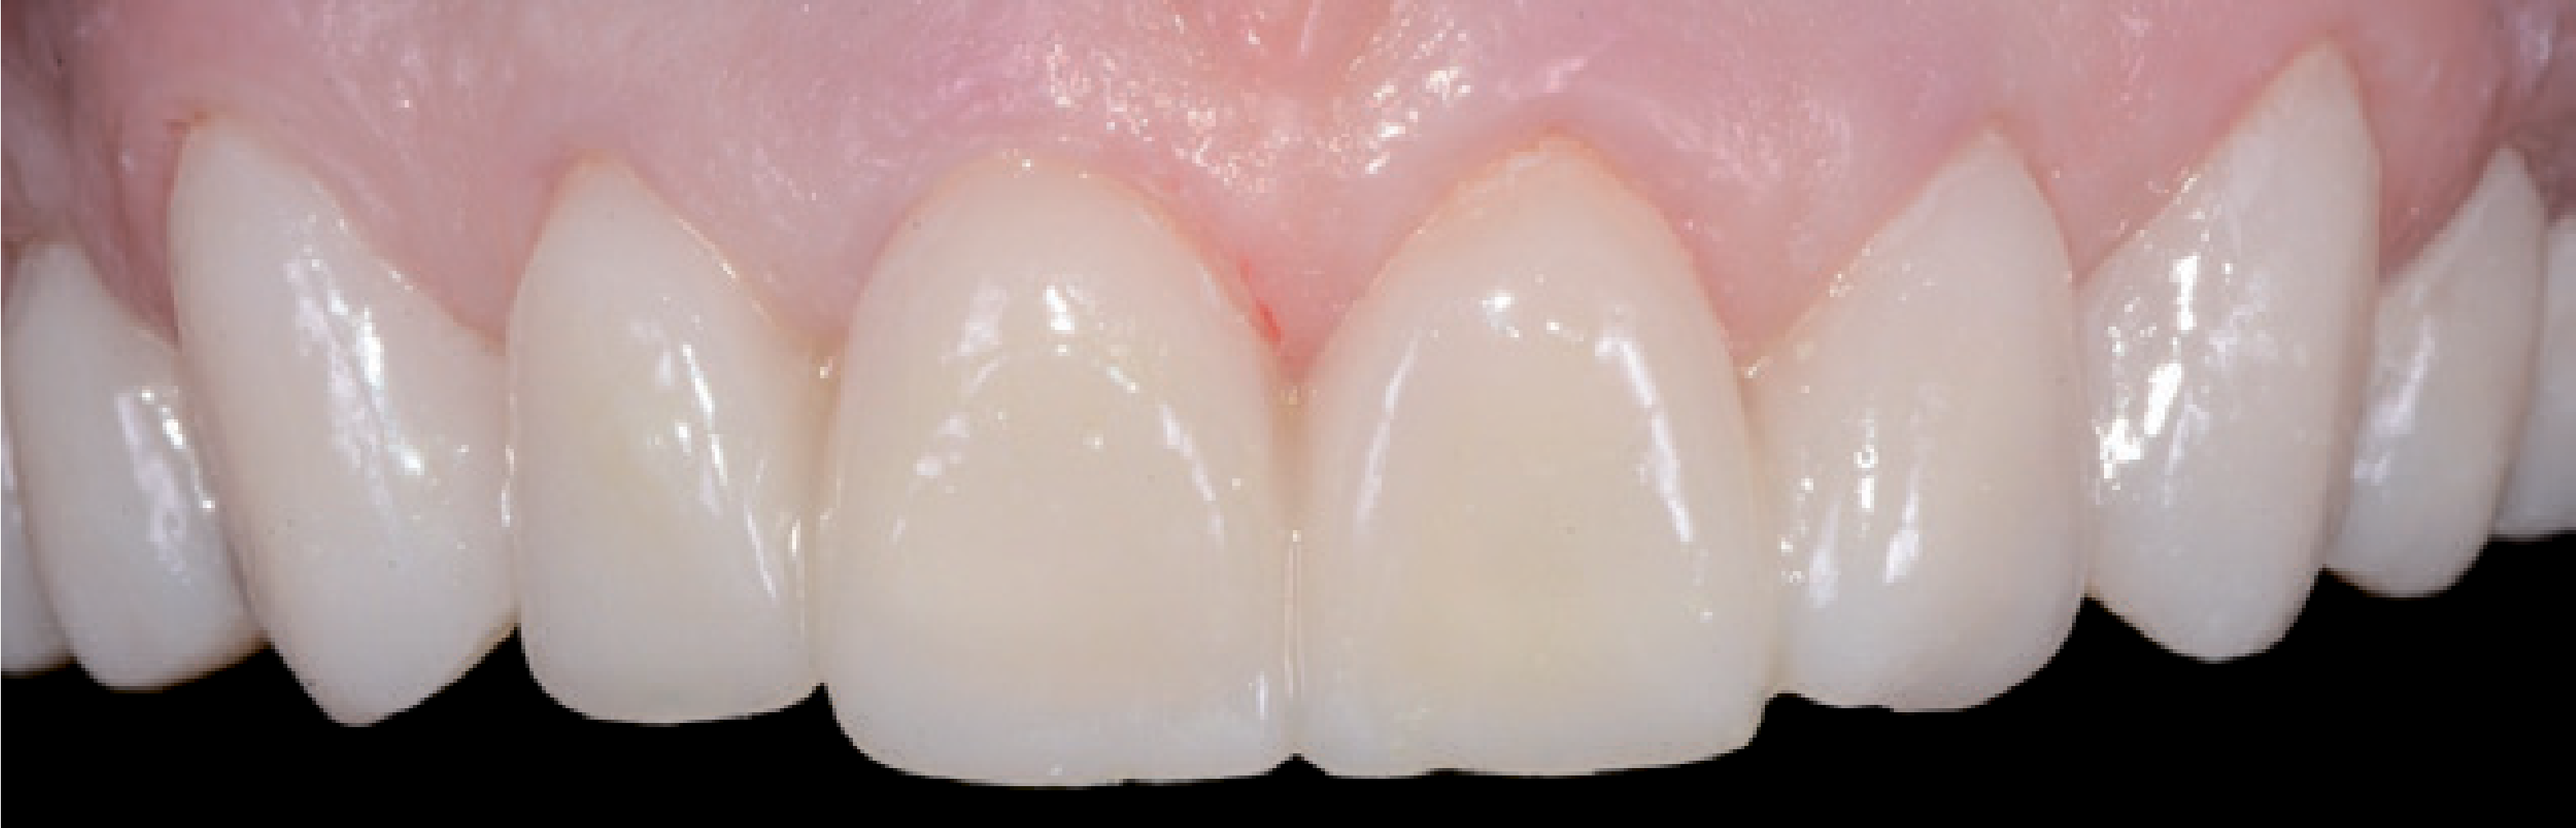

Коли посадка й колір вінірів були задовільними для пацієнта та лікаря, адгезивну фіксацію можна було виконати та отримати прогнозований результат. Кукси знову очистили струменем води, після чого зафіксували вініри. Вініри протравили 5% розчином фтористоводневої кислоти та силанізували системою з двох флаконів VitiqueSilane (DMG) для посилення міцності з'єднання. Протягом 20 секунд відпрепаровані ділянки перебували під впливом 37% фосфорної кислоти, щоб забезпечити адгезивне з'єднання з ТЕСО (DMG). Адгезивний засіб з одного флакона нанесли тонким шаром на 5 секунд. Перш за все, верхні центральні різці обробили одночасно, щоб гарантувати симетрію. Сусідні зуби закрили тефлоновою стрічкою (мал. 18).

За допомогою спеціальної канюлі для оброблення вінірів на протравлений кислотою вінір нанесли рівномірну й плоску смугу Vitique (DMG) – від різцевої до пришийкової зони (мал. 19).

Вініри акуратно встановили вручну. Для цього чинили тиск великим і вказівним пальцями у напрямку від різцевої до пришийкової зони. Коли реставраційні конструкції були остаточно встановлені (мал. 20), провели початкову полімеризацію кожного вініра з усіх боків протягом 1-2 секунд. Зайву кількість полімеризованого фіксаційного цементу в гелеподібному стані тепер можна було легко видалити за допомогою скалера. Далі провели остаточну фотополімеризацію кожного вініра з усіх боків протягом 40 секунд. Остаточне коригування маргінальних ділянок виконали за допомогою гумового полірувального інструмента. Потім всю процедуру встановлення вінірів провели повторно – на нижній щелепі, оптимізуючи естетичний результат і встановивши остаточний сагітальний різцевий шлях.